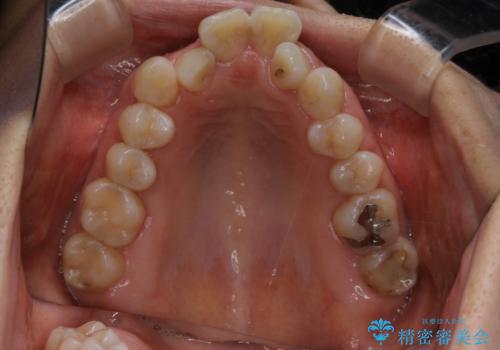

この患者様は骨格的に上あごが小さいことで問題が起きていたため、

上あごを骨ごと広げる必要がありました。

よって治療計画として、インプラントアンカーを使用した上顎急速拡大装置(MARPE)を使用することといたしました。

インプラントアンカーを使用した上顎急速拡大装置(MARPE)について

上あごの裏側(口蓋)に装置をマイクロインプラントで固定し、ネジを回すことで上あごを骨ごと広げていく装置です。

ご自身で回していただくのにコツが必要なのと、広がった直後は前歯に隙間ができてしまうことがあります。

治療中押されるような違和感がありますが、強い痛みはありません。